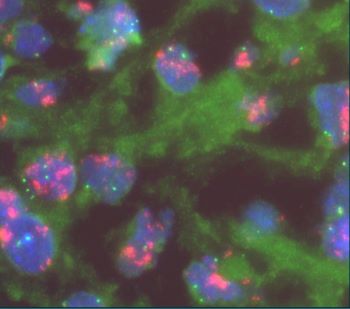

55 YOM presented with thigh mass. A biopsy was performed and showed the following lesion illustrated in the images. FISH analysis using a dual-color MDM2/CEN12 probe [Red=MDM2; Green=CEN12] was performed.

Similar to atypical lipomatous tumor/well-differentiated liposarcoma, supernumerary ring and giant marker chromosomes are the hallmarks of dedifferentiated liposarcoma detected in up to 90% of the cases. Ancillary study with immunohistochemical is positive for CDK4 and MDM2 (12q13-15 region) in nuclei of tumor cells in both the well-differentiated and the dedifferentiated component. Amplification of these genes can be detected by molecular genetic techniques. FISH analysis with dual-color probes is typically used to detect copy number changes in MDM2 gene and used to compare to CEN12 gene. A ratio of MDM2:CEN12 of more than 2 is interpreted as amplified MDM2. In addition to copying number changes in 12q13-15, chromosomal microarray shows recurrent gains in 12q24, 20q13, 6q22-q24, 9q33-q34, and losses in 13q14-q21, 11q22-q23.